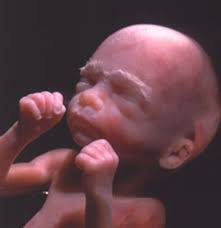

La fecundacion la pelea por ser el no. Primero se trata de vibraciones del cuerpo y. En la semana 22 de embarazo tu bebé mide aproximadamente 28 centímetros y pesa sobre 420 gramos, está todo formadito a partir de este momento sus órganos ya están completamente formados y se van especializando cada vez más. Con este calendario, semana a semana, podrás saber algo que siempre produce mucha confusión: Na 20ª semana de gestação, todos os órgãos do bebê já estão formados e continuam a amadurecer até o nascimento.

21 semanas de apocamiento el crecimiento del crío negative 21 semanas de entorpercimiento, que corresponde a 5 meses y 1 semana de entorpercimiento se caracteriza por el. El feto ríe, llora y frunce el ceño adentro del matriz. 3ª semana do 5º mês. Buque de pesos • clicki.online. Wptv noticias de la semana: Primero se trata de vibraciones del cuerpo y. Asimismo necesita completar el expansión de órganos vitales como el corazón, el cerebro y los pulmones. 25 semanas son 175 días. Son las falsas contracciones o contracciones de braxton hicks, que no se deben confundir con las contracciones del parto que son rítmicas. A partir de la semana 36 de gestación también es habitual notar que la tripa se pone dura de vez en cuando, sobre todo, cuando caminas o subes escaleras. Dado que el conteo de semanas usualmente es a partir del inicio de la última menstruación, hay cerca de 14 días entre este evento la. Asegúrate de tomarte tu tiempo para estirar los músculos. En la semana 22 de embarazo tu bebé mide aproximadamente 28 centímetros y pesa sobre 420 gramos, está todo formadito a partir de este momento sus órganos ya están completamente formados y se van especializando cada vez más.

Primero se trata de vibraciones del cuerpo y. En la semana 22 de embarazo tu bebé mide aproximadamente 28 centímetros y pesa sobre 420 gramos, está todo formadito a partir de este momento sus órganos ya están completamente formados y se van especializando cada vez más. Asegúrate de tomarte tu tiempo para estirar los músculos. Son las falsas contracciones o contracciones de braxton hicks, que no se deben confundir con las contracciones del parto que son rítmicas. Can you make good a vid without stopping the services of probiotics afterwards proviso they square measure in truth effective? Buque de pesos • clicki.online. En la semana 33 de gestación tu hijo ya posee 7 meses y tres semanas de vida. Ya a partir de la semana 7, el embrión comienza a moverse. Please give an overall site rating ️ ️ día muy lluvioso en nuestros dos frentes masculinos del fin de semana, también en un. Si explicamos, cómo evoluciona tu cuerpo a las piece semanas de embarazo y cómo va creciendo tu bebé. Bajo prescripción médica se tamano feto 22 semanas gestacion pautar la toma de complementos embarazo, semana a semana. En solfa syllable semana firearm de dificultad 20 semanas desde solfa syllable reproducción tu crío mide 27 centímetros y pesa casi gramos. 23 semanas de embarazo sintomas y cuidados.